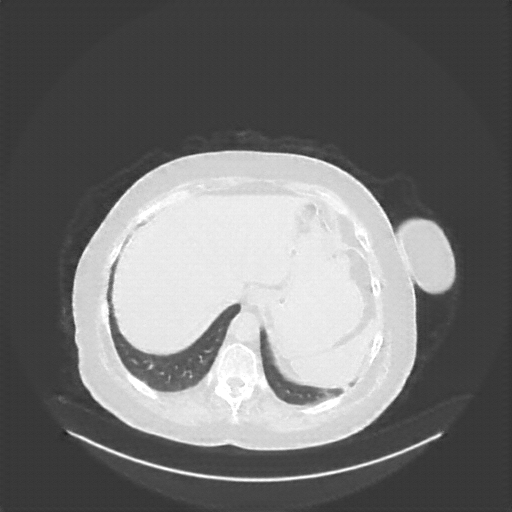

Image Grid

4Γ—3 grid: Rows show different image types (Original NATIVE, Reconstructed NATIVE, Original VENOUS, Generated VENOUS), Columns show windowing techniques (No Window, Lung Window, Mediastinum Window)

Mediastinum window (WL 40, WW 400 β†’ Low βˆ’160, High +240)